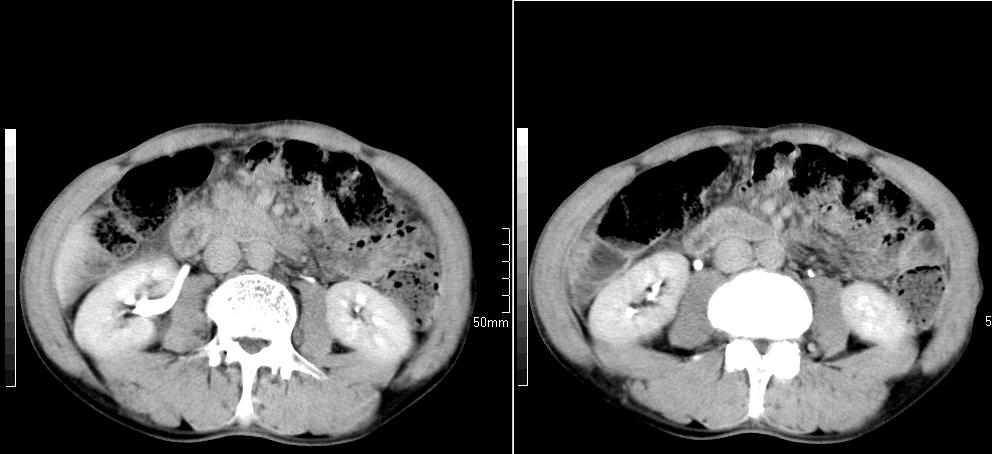

标题: CT26769:男,58岁,腹胀、腹部不适一年余 [打印本页]

标题: CT26769:男,58岁,腹胀、腹部不适一年余

肠系膜脂膜炎,胆囊炎,脾大。建议结合临床。鉴别:慢性胰腺炎并假囊肿形成。

1 慢性胰腺炎并假囊肿形成。2 慢性胆囊炎并累及肝边缘!

1)考虑慢性胰腺炎并假性囊肿形成。2) 慢性胆囊炎。3)肝内胆管扩张。

1肝内胆管扩张,性质待定,2慢性胰腺炎胰管扩张,胰腺颈部假囊肿,3肝左叶低密度为小囊肿,4胆囊炎。